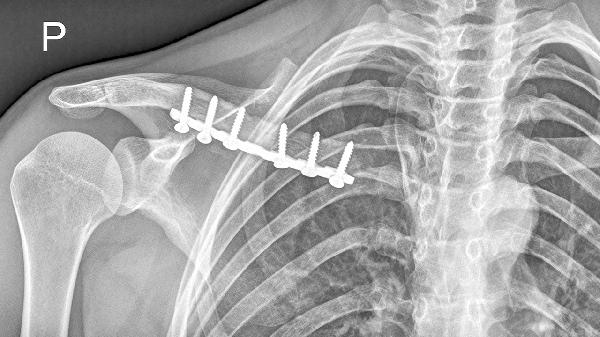

锁骨骨折恢复期需保持均衡饮食结构,建议分5-6次少量进食减轻胃肠负担。适当增加猕猴桃、草莓等维生素C丰富的水果促进胶原合成,同时配合医生指导的康复训练。避免吸烟饮酒等影响骨愈合的不良习惯,定期复查X线观察骨痂生长情况。睡眠时保持30°半卧位可减少骨折端移位风险,日常活动需佩戴锁骨固定带保护。